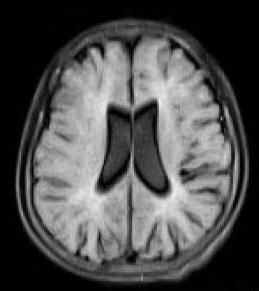

頭顱核磁共振圖像

magnetic resonance imaging,MRI,PMD 影像學主要表現是髓鞘發育不良或髓鞘完全無發育。頭顱MRI可顯示髓鞘化異常,主要表現在腦白質T2 加權像和Flair 像瀰漫性高信號,此項檢查對PMD 診斷具有重要意義。因為生後第1、2 年是腦白質髓鞘化形成的重要時期,所以此時頭顱MRI 表現特異性相對較小。但因正常3 個月嬰兒的內囊後肢、胼胝體壓部和視放射區已經有髓鞘形成,所以早期這些部位異常對PMD 診斷具有重要意義。隨著PMD 患兒年齡逐漸增加,其腦白質發育極其落後,頭顱MRI 表現為新生兒樣腦白質表現,T1 加權像腦白質改變常不明顯,T2 加權像腦白質幾乎全部為高信號。隨著病情進展,腦白質容積縮小,表現為胼胝體變薄,腦室擴大和皮質內陷。痙攣性截癱患兒腦白質異常程度較PMD輕,其頭顱MRI T2 加權像可表現為片狀高信號。